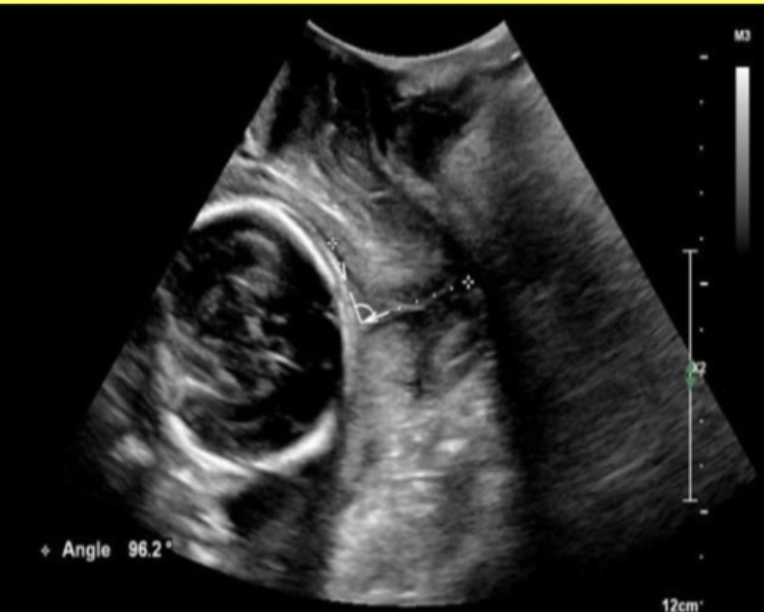

while performing an anatomy scan on a 22w fetus, you are unable to obtain a cross-sectional image of the umbilical cord to show the number of umbilical arteries.

what is an alternative method to evaluate the arterial anatomy of the cord

a) obtain a cross-section view of the umbilical cord insertion at the placenta + apply color doppler

b) obtain a transverse view of the fetal abd at the level of the kidneys + apply color doppler

c) obtain a transverse view of the fetal pelvis at the level of the bladder + apply color doppler

d) obtain a midline sagittal view of the fetus that includes the fetal bladder + apply color doppler